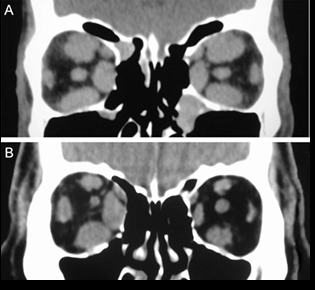

Imagen en orbitopatia tiroidea

Agrandamiento bilateral de músculos extraoculares

Tc en orbitopatia tiroidea

Agrandamiento músculos extraoculares, exoftalmos, nervio óptico estirado

RM en orbitopatia tiroidea

T1: agrandamiento músc extraoculares

T2: aumento señal en musculos extraoculares en fases agudas

Diametro disminuido nervio óptico